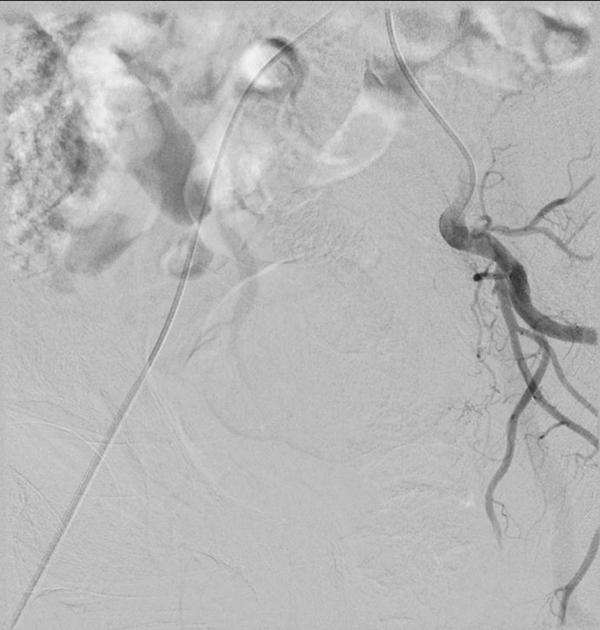

套上厚重的铅衣,站在明亮的无影灯下,两位主任开始了紧张而又有条不紊的介入手术。将一根1毫米粗的穿刺针穿刺入股动脉后,依次送入血管鞘、导丝、导管,再通过导管造影,膀胱癌就原形毕露了,肿瘤的供血动脉也清晰可见。

在透视镜的辅助下,将一根更细的微导管送入到肿瘤的供血动脉后,通过微导管将血管栓塞剂注入肿瘤供血动脉,再次造影,显示:膀胱癌的肿瘤染色已经完全消失不见。

这也就意味着膀胱癌的供血基本没有了,尿血症状也就能够得到控制。